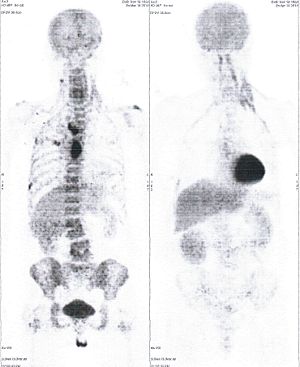

Below are some of the cases, from more than 80 cases we have treated so far with good results. When reading the PET/CT scans, the picture on the left is before treatment, and the picture on the right is after treatment. The intensity of black represents the activity of the cancer, but some black areas are not cancer: brain, heart, radioactive urine in bladder. For the heart, the intensity of black depends on the number of hours of fasting: if more than 10 hours, the heart is not even black, but if fasting is less than 6 hours, it is very black. The intensity of black in the brain can be variable in different scans depending on the brain activity at the time of the scan. The intensity of black in the radioactive urine can also be variable due to the hydration of patients and the time of injection of diuretic.

CASE NO: 1

(HEPATOCELLULAR CARCINOMA + STOMACH CANCER)

A middle-aged women who is very thin and very weak, can hardly walk, lying in bed most of the time. She saw a cancer specialist in a top hospital who discovered that she had massive hepatocellular carcinoma, and another cancer in the stomach. Given that hepatocellular carcinoma is incurable and stomach cancer is very difficult if not impossible to cure without surgery, she was told that nothing could be done for her. She came to ask us to help her. After just 4 treatment, the hepatocellular carcinoma went into remission, and the stomach cancer (arrow) became less active. Until today, more than 6 months later, the hepatocellular carcinoma is still in remission.

CASE NO: 1 - A FEW MONTHS LATER

A few months after successful treatment for hepatocellular carcinoma, and partially successful for stomach cancer, the PET/CT scan showed the stomach cancer becoming very active, with several metastases to the parts of the liver not previously involved by hepatocellular carcinoma. After a few treatment, all the active stomach cancer lesions in the stomach and in the liver went into remission.